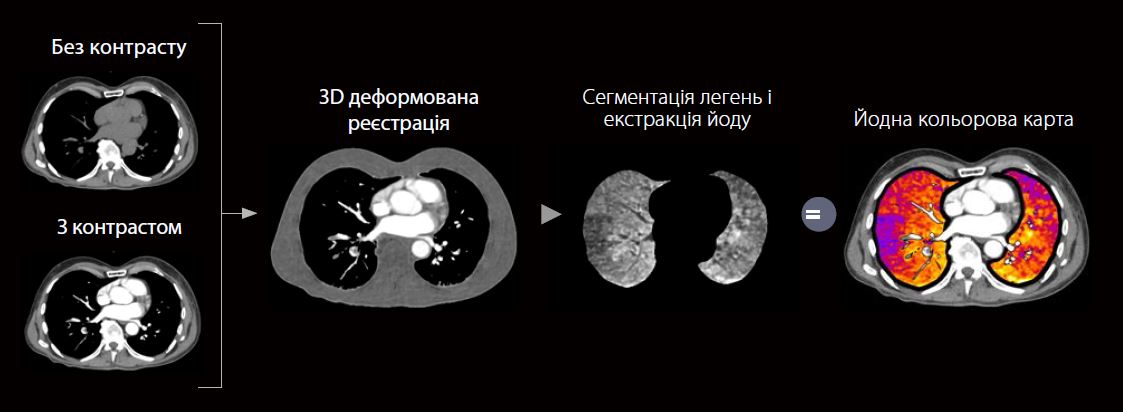

Збір даних

Модель КТ: Aquilion Serve

Режим сканування: Ultra Helical Subtraction

Колімація: 0.5 мм × 80

Експозиція: 120 kV, SURE Exposure

Швидкість ротації: 0.35 сек.

CTDIvol: 1.6, 2.0 мГр

Total DLP: 126.9 мГр∙cм

Доза: 1.78 мЗв

k-фактор: 0.014*

• Доступний для будь якого КТ з одним джерелом експозиції

• Автоматична обробка та передача зображень

• Показує локальний розподіл йоду

• Виявлення/виключення посилення контрастності

• Визначте місцеві відмінності перфузії